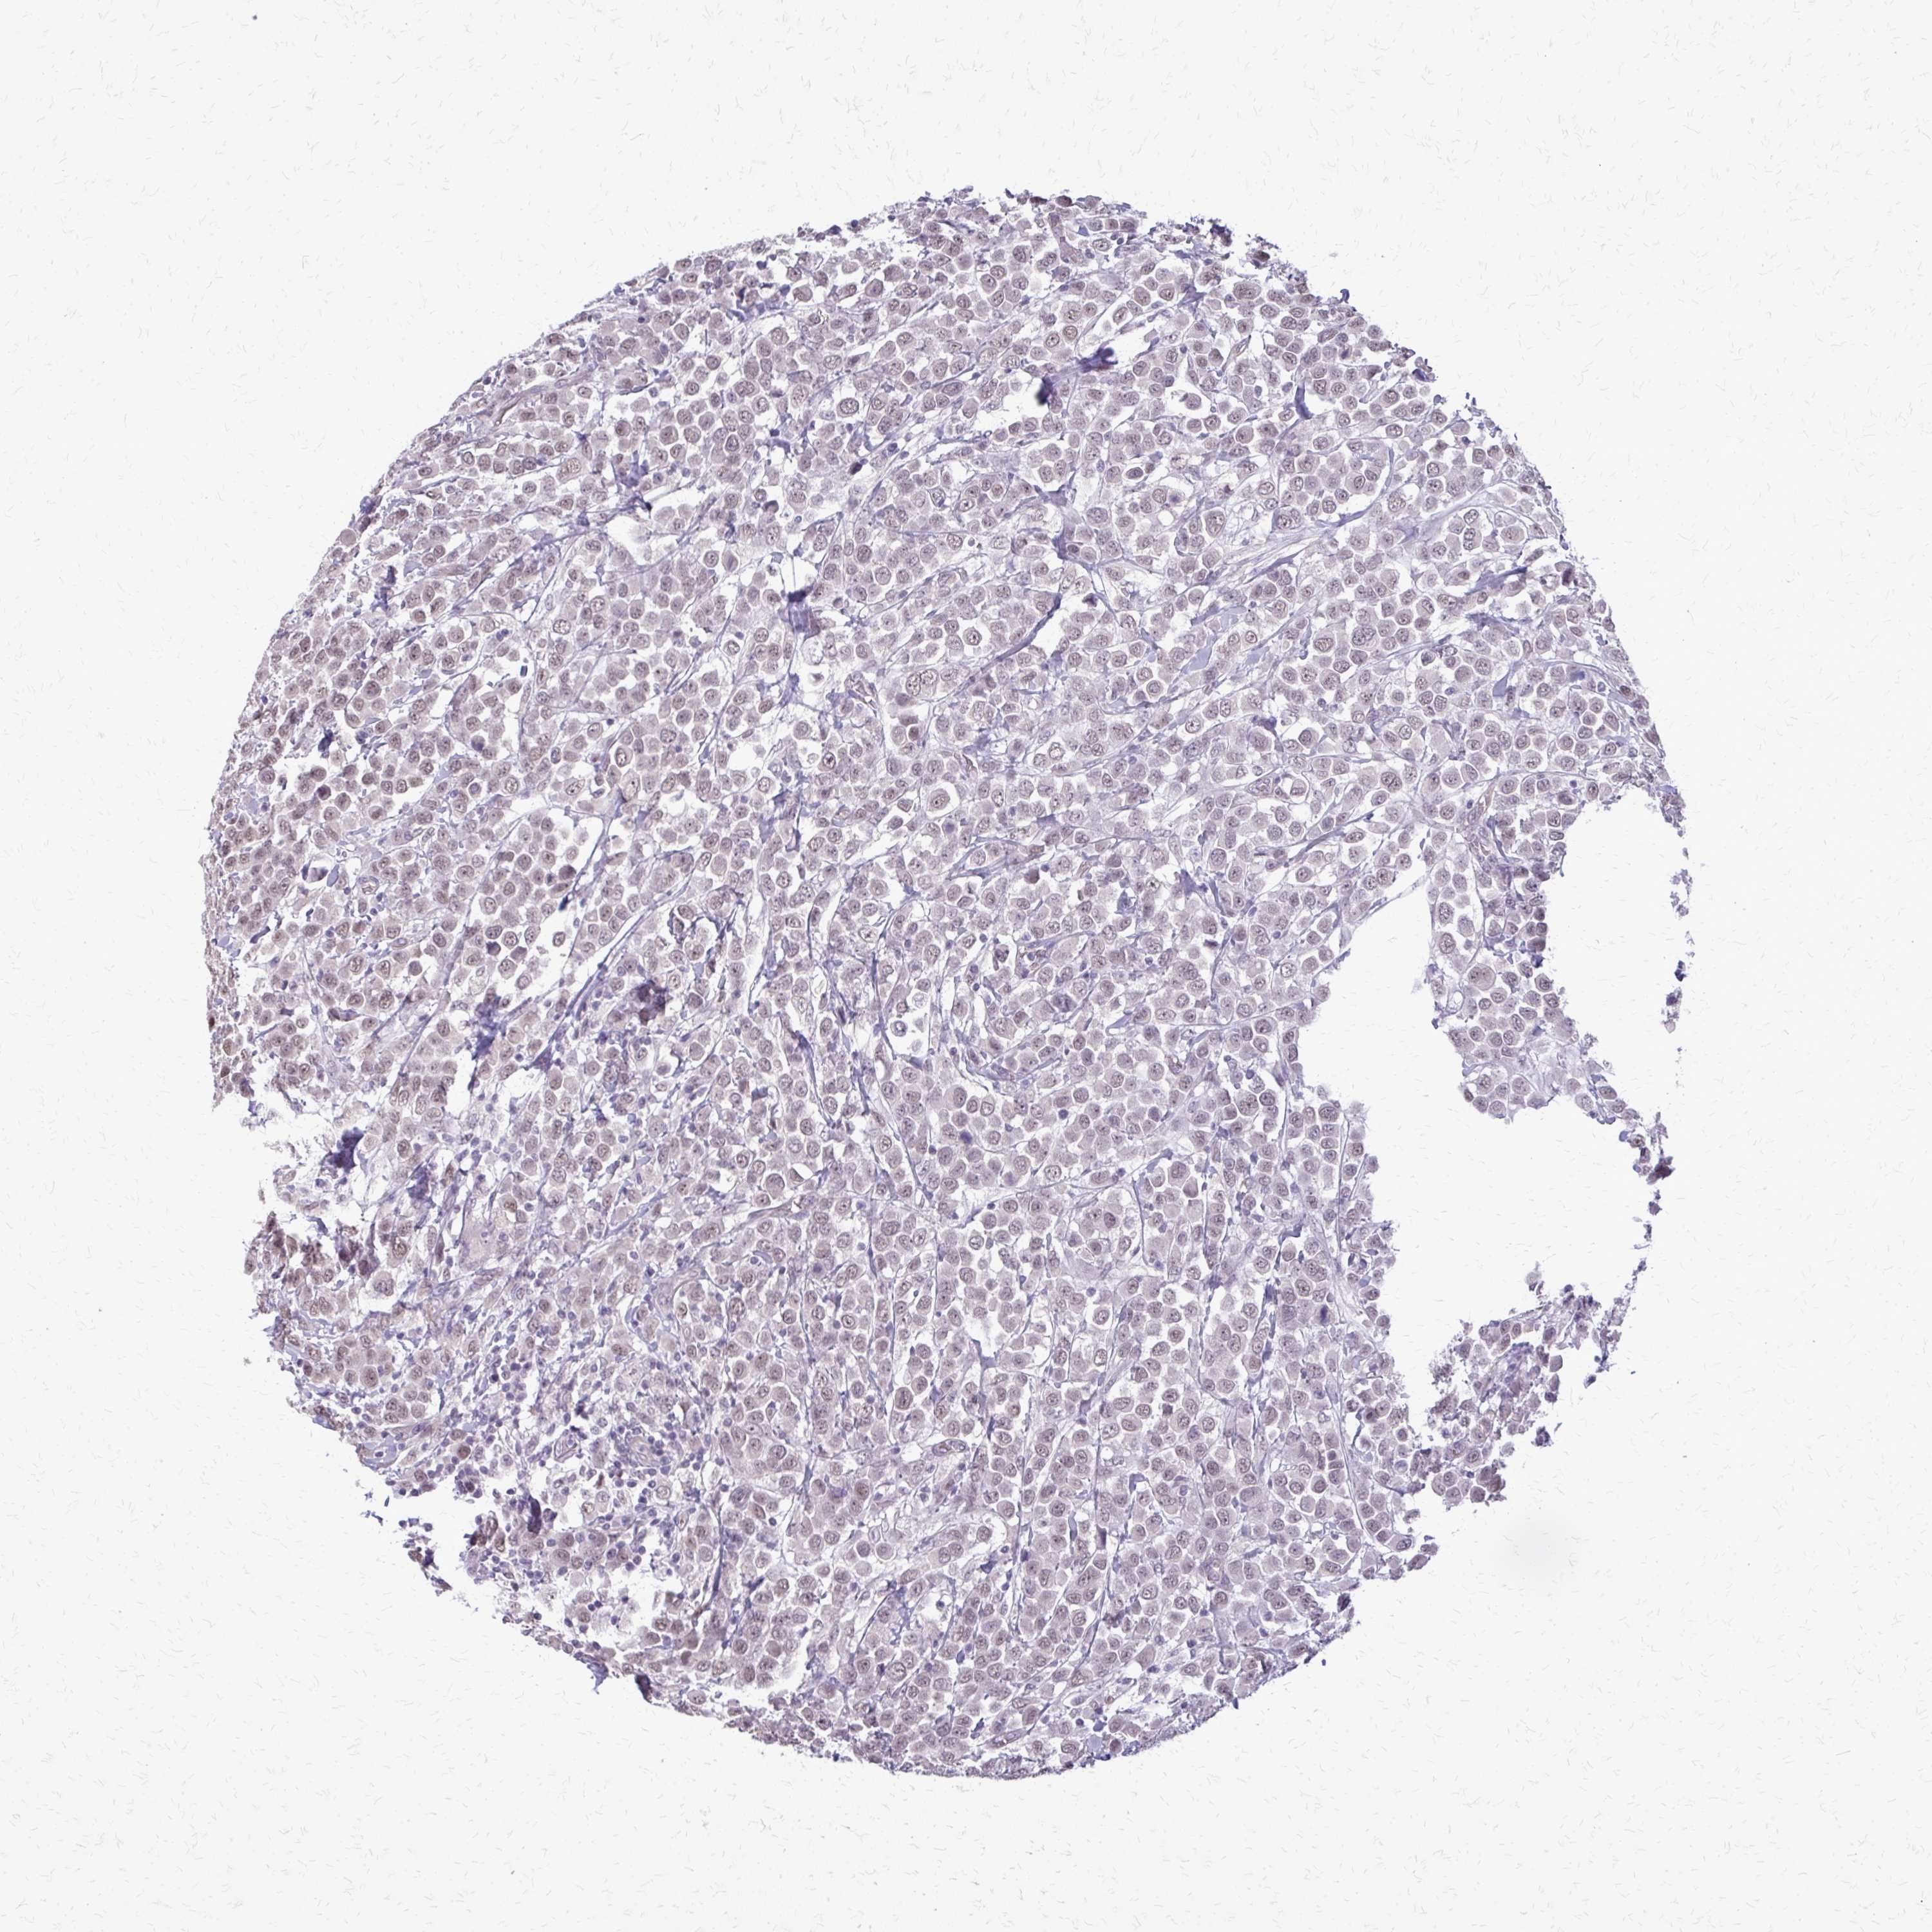

BRCA TCGA BRCA VALIDATION PROTEIN EXPRESSION